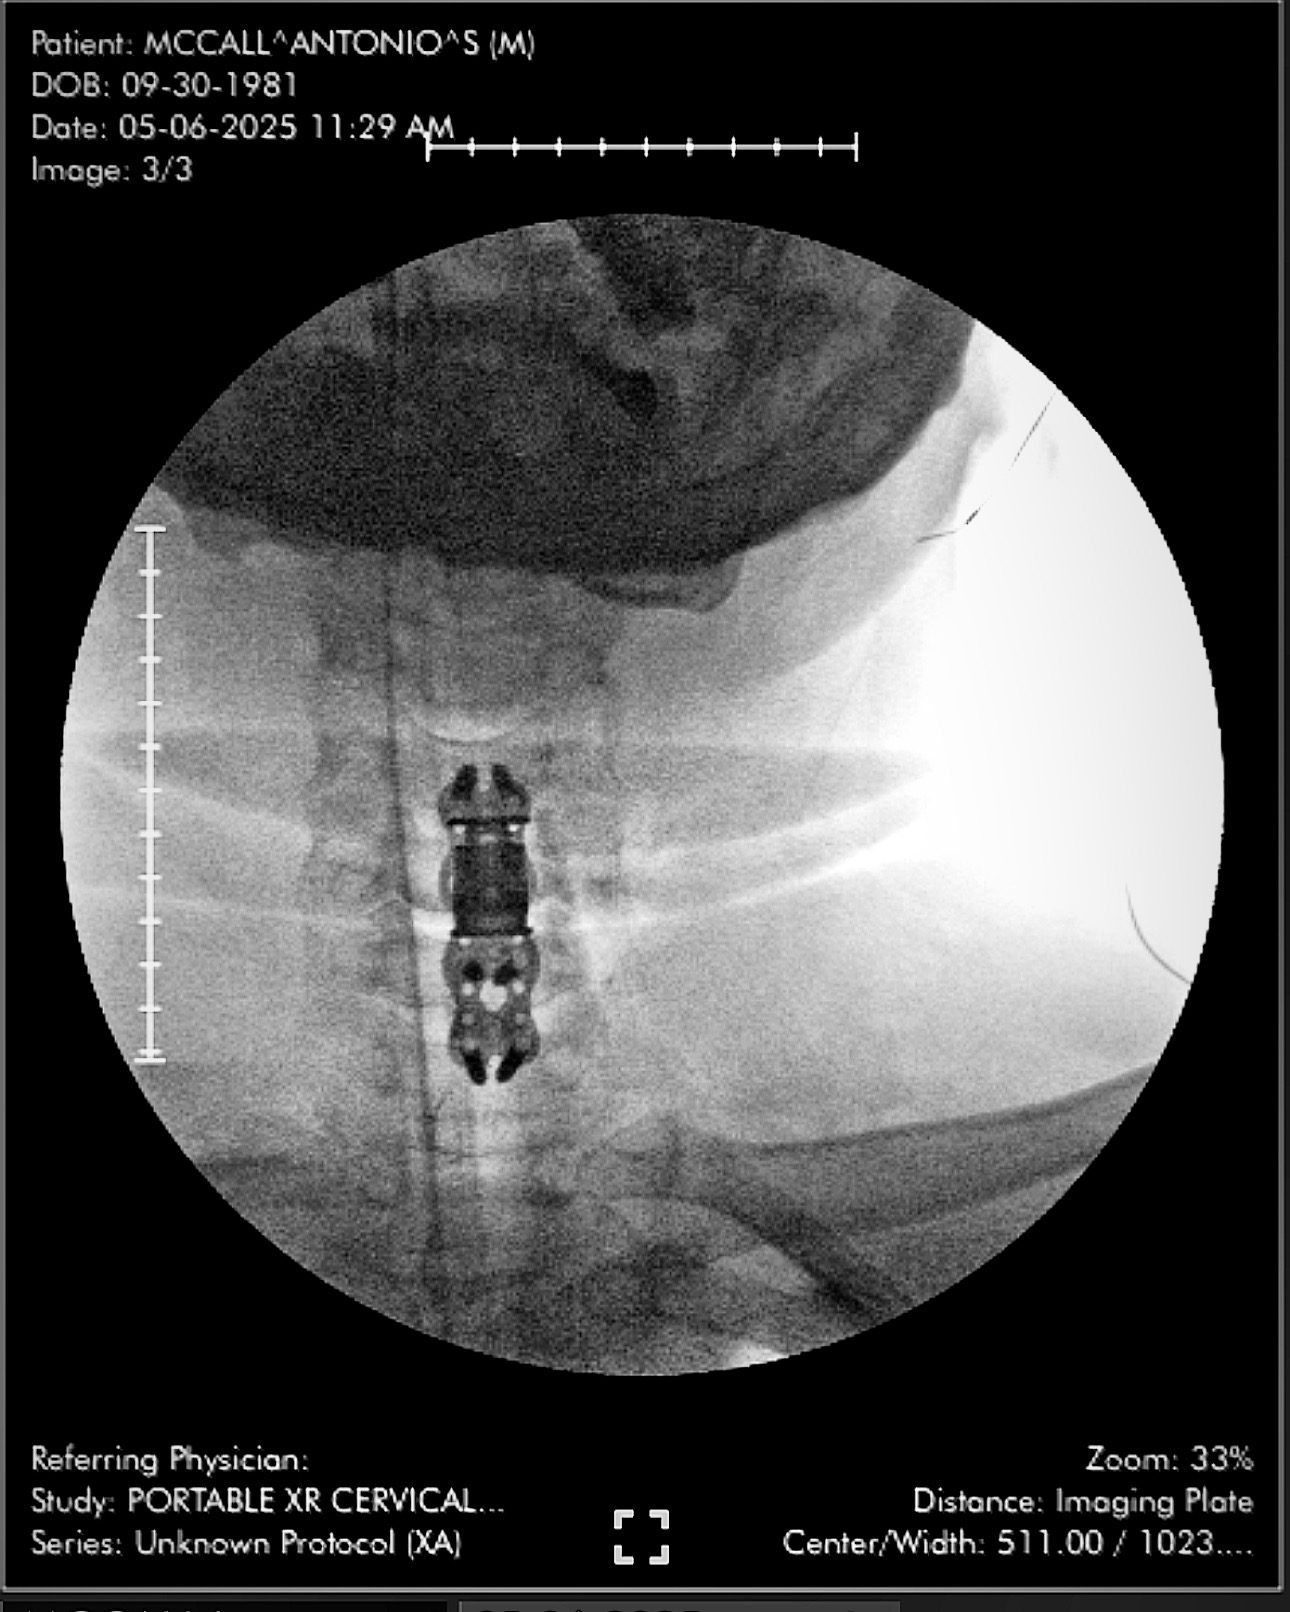

My name is Antonio McCall. September 26th, 2024 I had a total hip replacement surgery, since then, my hip has recovered but there were complications unknown to anyone which led to me needing another surgery about a week ago, this one on my spine (2 level ACDF)